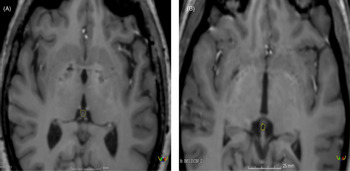

Volumetric measurements of each pineal gland were manually drawn via slice-by-slice segmentation using the ‘Draw Effect’ tool in the axial plane, with simultaneous side-by-side view of the sagittal and coronal plane. The sum of these areas was added up to determine the volumes of the pineal gland. The total pineal gland area was obtained using ’Segment Statistics’ module to determine the real volume (RV) of the pineal gland in cubic millimetres (see Fig. 1). The cyst pineal volume (CPV) was also measured following the same procedure used to measure the RV (see Fig. 1). Additionally, the reference value of the pineal gland volume (TPV) was estimated using the Hasegawa method by the formula 0.5 × H × L × W (where W is the maximum width, L is the maximum length and H is the maximum height of the gland; Hasegawa et al., Reference Hasegawa, Ohtsubo and Mori1987).

Fig. 1. T1-weighted Turbo Field Echo (T1-w TFE) imaging of pineal region illustrating: (A) solid pineal gland measured manually (hiperintense) and (B) cystic pineal gland measured manually (hipointense).

PPV was calculated as the subtraction of CPV-RV in the cases where cysts were found. Moreover, when no cyst was observed the PPV was calculated as follows: PPV = RV. Pineal calcifications were not estimated when using T1 sequences, since it does not allow a reliable identification (Adams et al., Reference Adams, Böker, Bender, Diederichs, Fallenberg, Wagner, Hamm and Makowski2017).